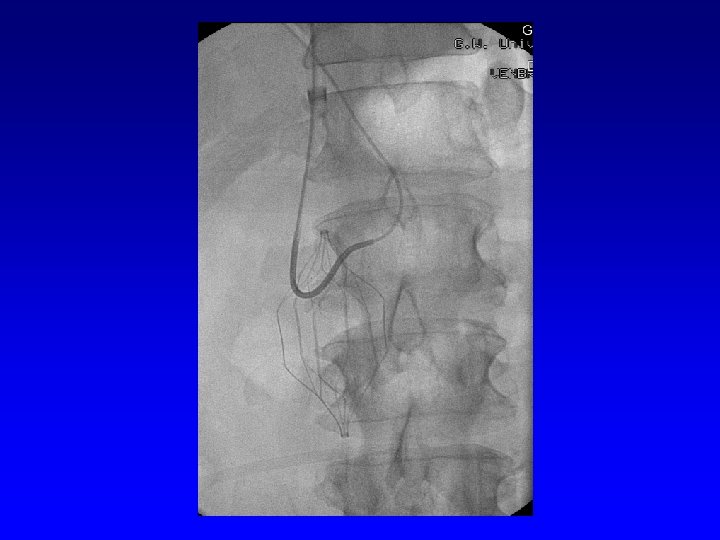

Retrieval with a “grasping”device Recovery Filter, G 2 (Bard Peripheral Vascular) Aln (Aln Implants)

G 2 Filter Cone Bard Peripheral Vascular.

Bard Peripheral Vascular.

Recovery (G 2) Retrieval